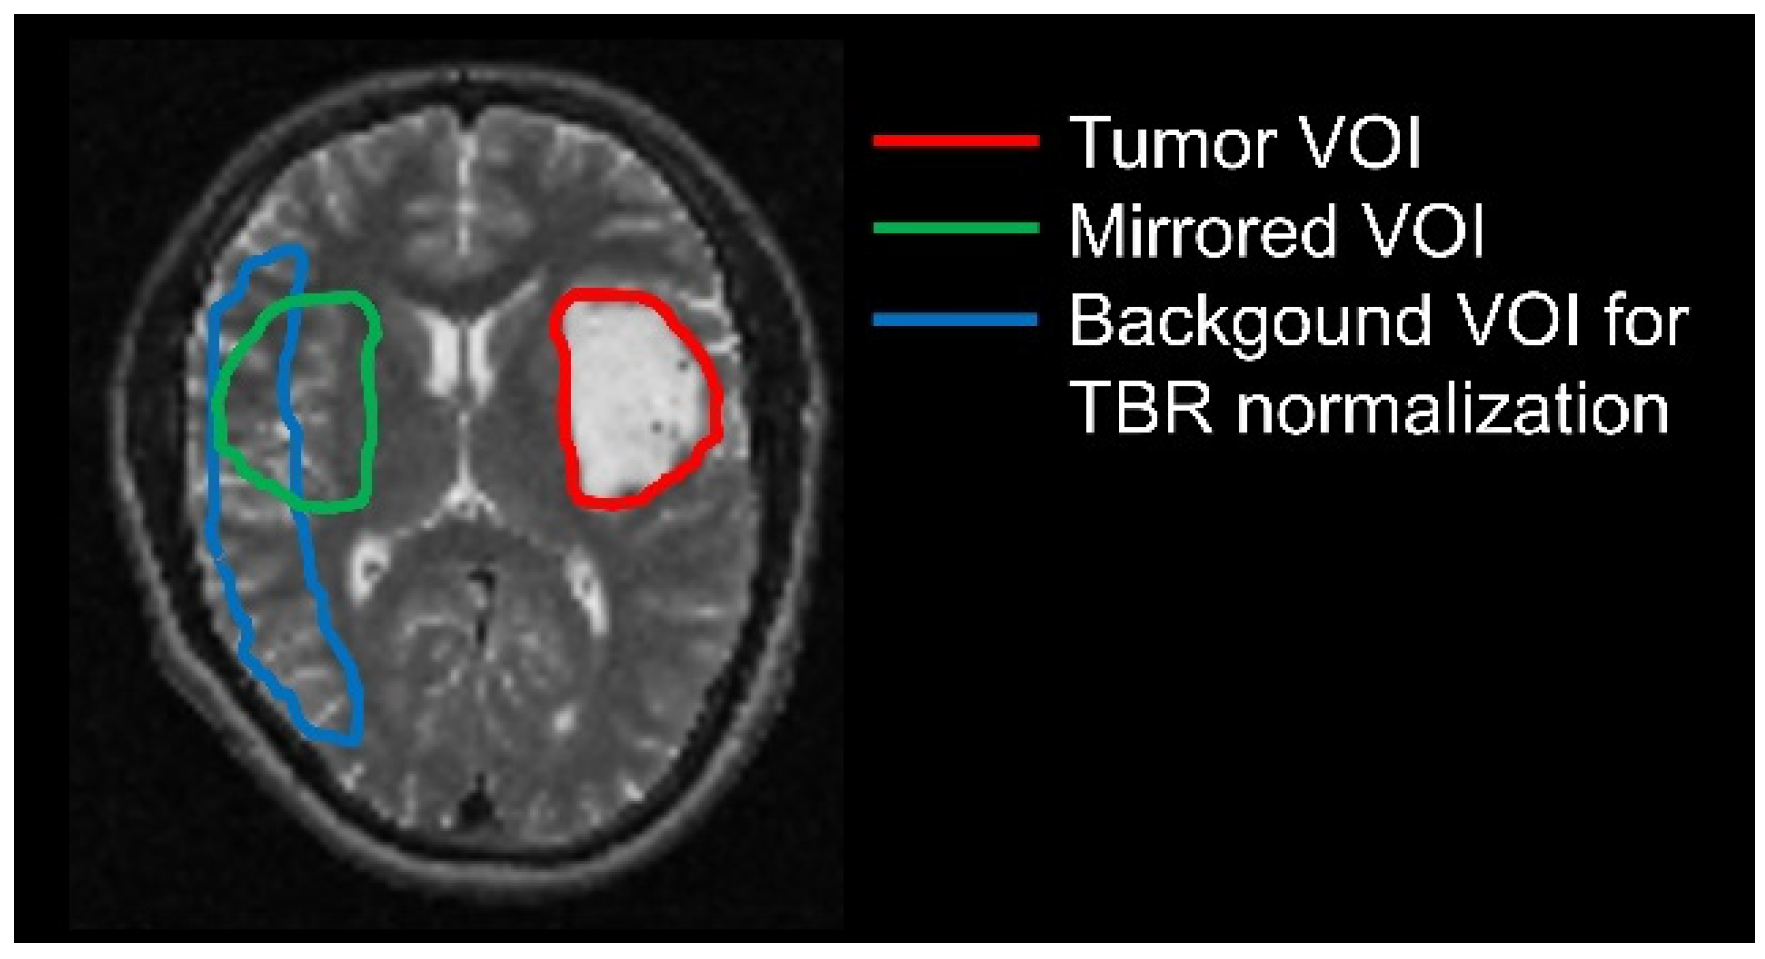

2.4. Delineation of Tumor and Background Volumes